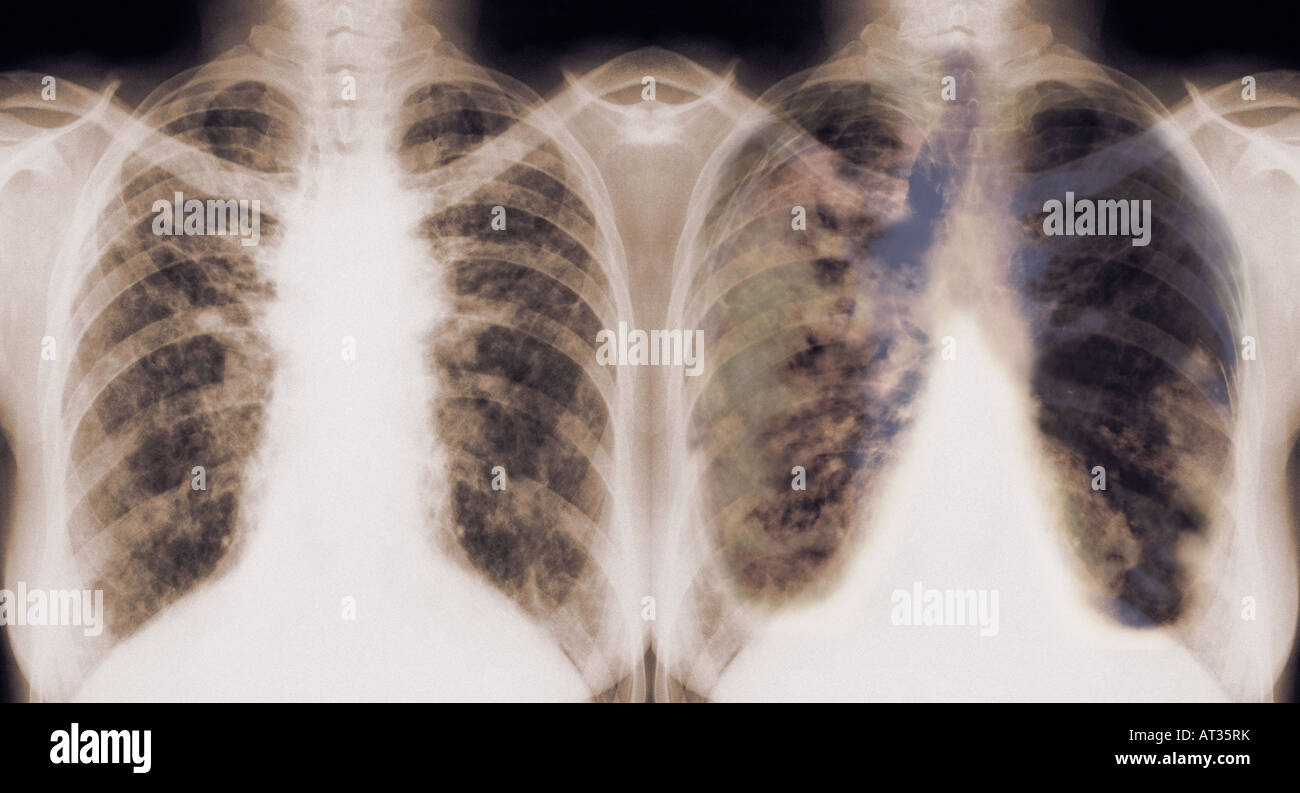

From www.alamy.com

Normal and Cancerous Lungs, Xray Stock Photo Alamy What Color Should Lungs Be On X Ray Airway, breathing, cardiac, diaphragm and everything else. If the lungs look like they have regions of density within them, that’s something to take note of. 5 when the patient inspires. darker colors indicate less dense material, and lighter colors indicate more dense material. This web page covers pa and lateral views, silhouette sign,. The lungs appear black because they. What Color Should Lungs Be On X Ray.